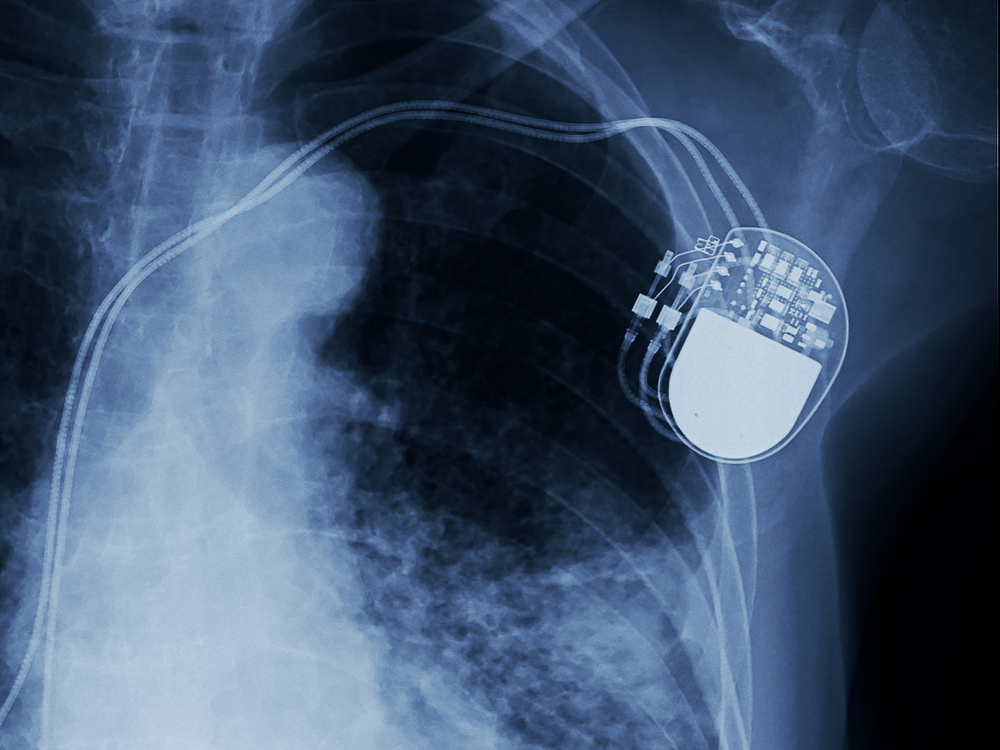

Beberapa orang mungkin perlu dipasangkan alat pacu jantung (pacemaker) untuk mengelola fungsi jantung mereka yang sudah tidak sebaik dulu. Alat pacu jantung adalah sebuah perangkat kecil seukuran kotak korek api yang ditanam di bawah kulit dada untuk mengontrol detak jantung. Lantas, siapa saja yang butuh alat tersebut dan seperti apa prosedur pemasangan alat pacu jantung?

Alat pacu jantung adalah sebuah perangkat sistem monitor internal yang dipasang pada jantung untuk mengukur aktivitas listrik, pola denyut, detak jantung, serta temperatur darah yang dipompa oleh jantung. Namun, tidak semua orang butuh dipasangkan alat pacu jantung.

Alat pacu jantung bekerja meniru aksi impuls listrik alami jantung Anda. Untuk menjalankan fungsi tersebut, pacemaker terbuat dari dua bagian:

- Generator. Bentuknya adalah kontainer logam kecil yang menyimpan baterai untuk memproduksi sirkuit listrik guna mengatur laju impuls listrik yang dikirim ke jantung Anda.

- Kabel timah (elektroda) yang terdiri dari satu sampai tiga kabel fleksibel. Masing-masing ditempatkan di bilik-bilik jantung Anda. Fungsinya menyalurkan sinyal elektrik untuk menyesuaikan denyut jantung Anda.

Sementara itu, generator alat pacu akan diselipkan lewat sayatan di bawah kulit tepat di bawah tulang selangka setelah kawat timah terpasang ke generator. Umumnya, generator akan ditempatkan di sisi yang tidak dominan. Jadi apabila Anda tidak kidal, perangkat akan ditempatkan di dada kiri atas. Jika Anda kidal, perangkat akan ditempatkan di dada kanan atas Anda.